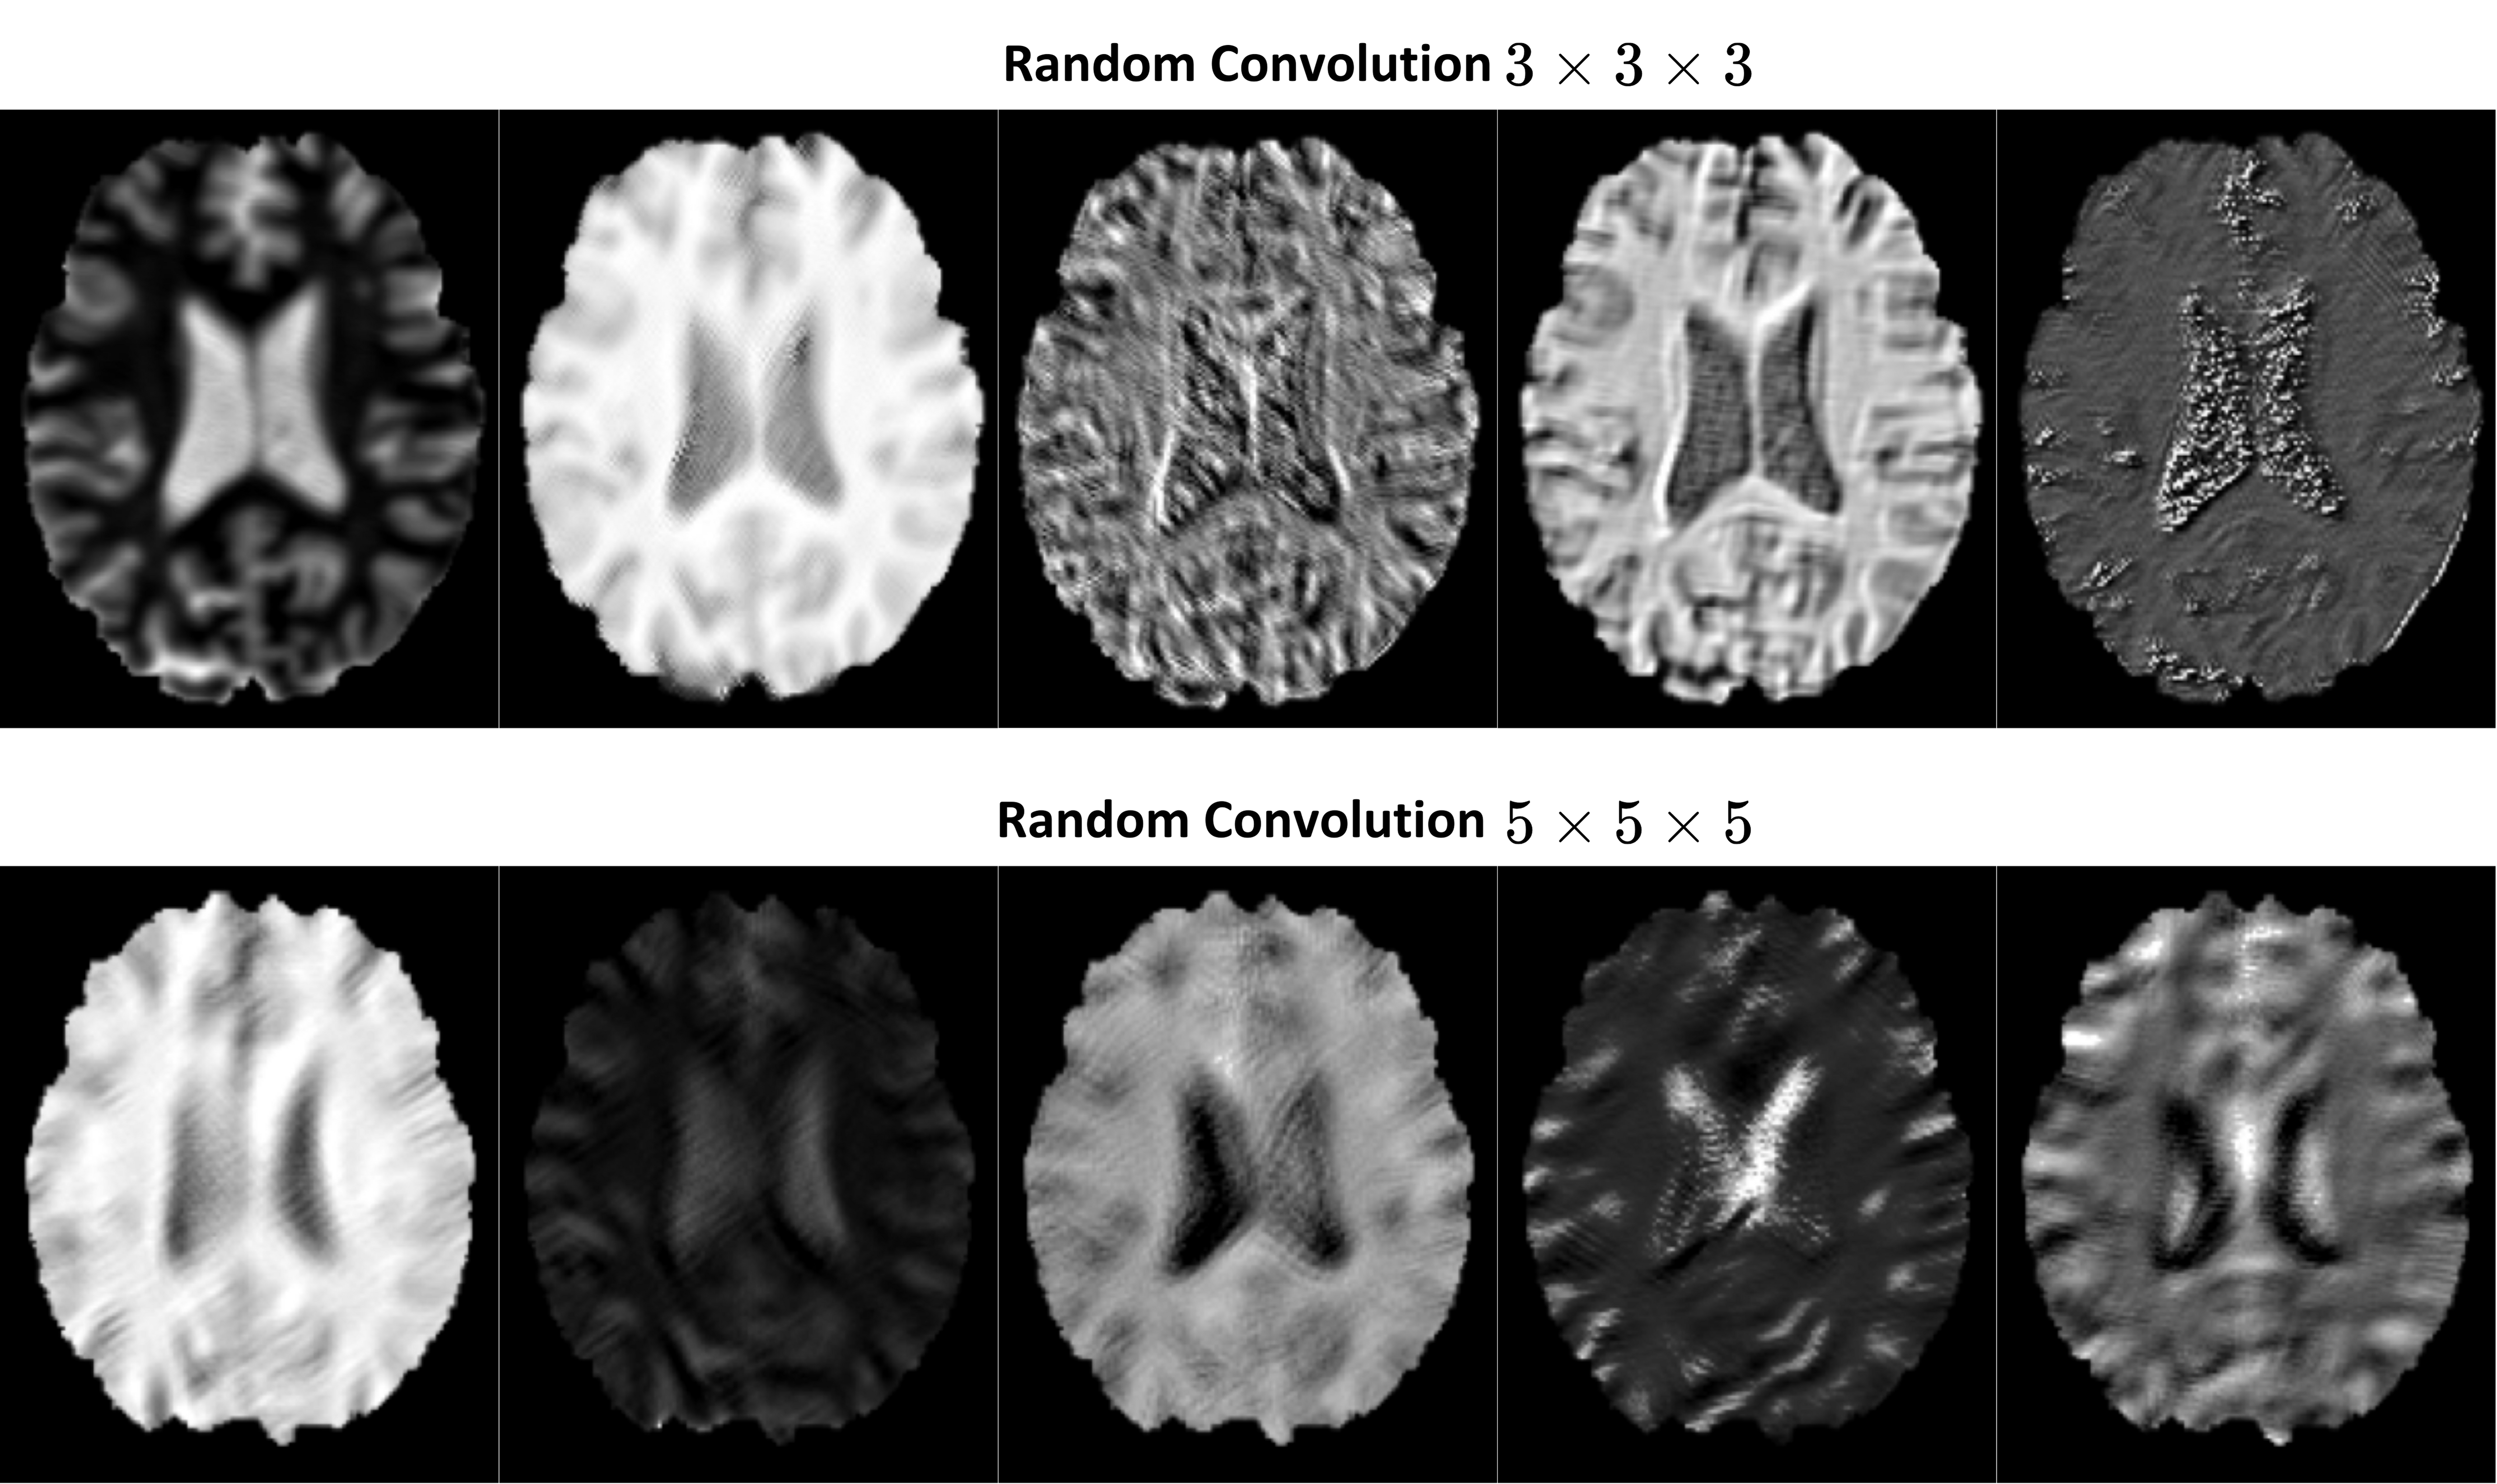

3.4 Contrast and Geometric Augmentation

To develop a contrast-agnostic registration framework, we introduce a method that emulates a wide range of image contrasts using random convolution (RC) [65] for contrast augmentation in 3D radiological tasks for the first time. RC has been beneficial in creating robust representations for domain generalization across both computer vision and medical imaging tasks in 2D, such as segmentation and classification [49, 62, 40]. This technique utilizes randomly initialized convolutional filters to modify the visual characteristics of input images while preserving their geometric and structural integrity. Previous research indicates that using large kernels in RC can lead to blurring, which can be problematic for registration tasks that depend on detailed image features to establish pixel-level correspondences. To address this issue, we employ a 1×1×11111\times 1\times 11 × 1 × 1 kernel size to minimize artifacts and retain structural details. To cover a broad range of contrast variations, we sequence a set of RC layers with LeakyReLU activation, enabling the network to model complex, non-linear intensity relationships among various MRI contrasts. The convolutional kernel parameters in each RC layer are independently drawn from uniform distributions, ensuring a broad range of contrast transformations. RC enables the network to learn landmarks in a contrast-invariant manner, helping to improve the generalization and stabilize the training process. Samples of contrast-augmented scans with RC are shown in the Supplementary Materials. Moreover, we performed random affine augmentations on the scans as our geometric augmentation during training. This augmentation ensures that the model learns to detect landmarks accurately, even under varying spatial configurations, improving generalization to unseen data.

All learning-based methods were implemented using PyTorch. We utilized the Adam optimizer with an initial learning rate of 104superscript10410^{-4}10 start_POSTSUPERSCRIPT - 4 end_POSTSUPERSCRIPT and a cosine annealing scheduler with a minimum learning rate of 106superscript10610^{-6}10 start_POSTSUPERSCRIPT - 6 end_POSTSUPERSCRIPT. To balance computational efficiency, M𝑀Mitalic_M was set to 2. The model was trained for 2500 epochs. Also, we used TPS as our deformation field (Tβsubscript𝑇𝛽T_{\beta}italic_T start_POSTSUBSCRIPT italic_β end_POSTSUBSCRIPT ) model and mean-squared error (MSE) as a similarity loss function (simsubscriptsim\mathcal{L}_{\text{sim}}caligraphic_L start_POSTSUBSCRIPT sim end_POSTSUBSCRIPT). For TPS, the regularization parameter (λ𝜆\lambdaitalic_λ) was randomly sampled from a log-uniform distribution ranging between 0 and 10. For random affine augmentation, the parameters are uniformly sampled as follows: rotations within [180superscript180-180^{\circ}- 180 start_POSTSUPERSCRIPT ∘ end_POSTSUPERSCRIPT, +180superscript180+180^{\circ}+ 180 start_POSTSUPERSCRIPT ∘ end_POSTSUPERSCRIPT], translations between [1515-15- 15, 15151515] voxels, scaling factors in [0.80.80.80.8, 1.21.21.21.2], and shear values in the interval [0.10.1-0.1- 0.1, 0.10.10.10.1]. Lastly, the RC-based contrast augmentation includes five RC layers, each with kernel weights drawn from a random uniform distribution U(0,2)𝑈02U(0,2)italic_U ( 0 , 2 ). After sampling, these kernel weights are adjusted to be zero-centered. Each RC layer is followed by a LeakyReLU activation function with a negative slope of 0.2.